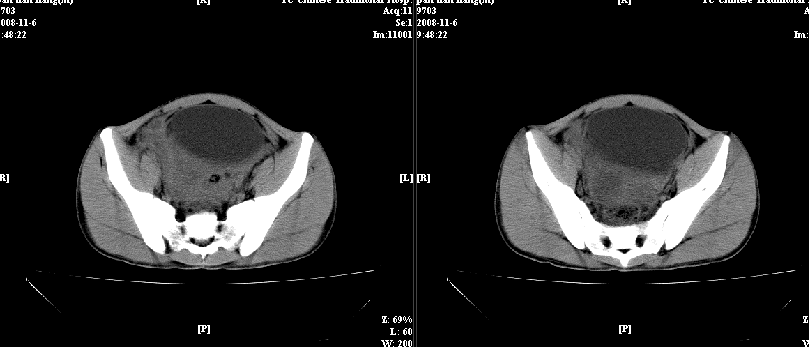

以下是引用dxm在2008-11-6 13:32:00的发言:[br]膀胱直肠窝积液 盲肠璧增厚 小肠淤积

以下是引用zsl6918在2008-11-6 14:13:00的发言:[br]如果阑尾炎病史明确,那腹腔及盆腔改变考虑脓肿形成.

以下是引用zjzjr在2008-11-6 14:37:00的发言:[br]支持阑尾炎伴盆腔及右髂窝脓肿形成